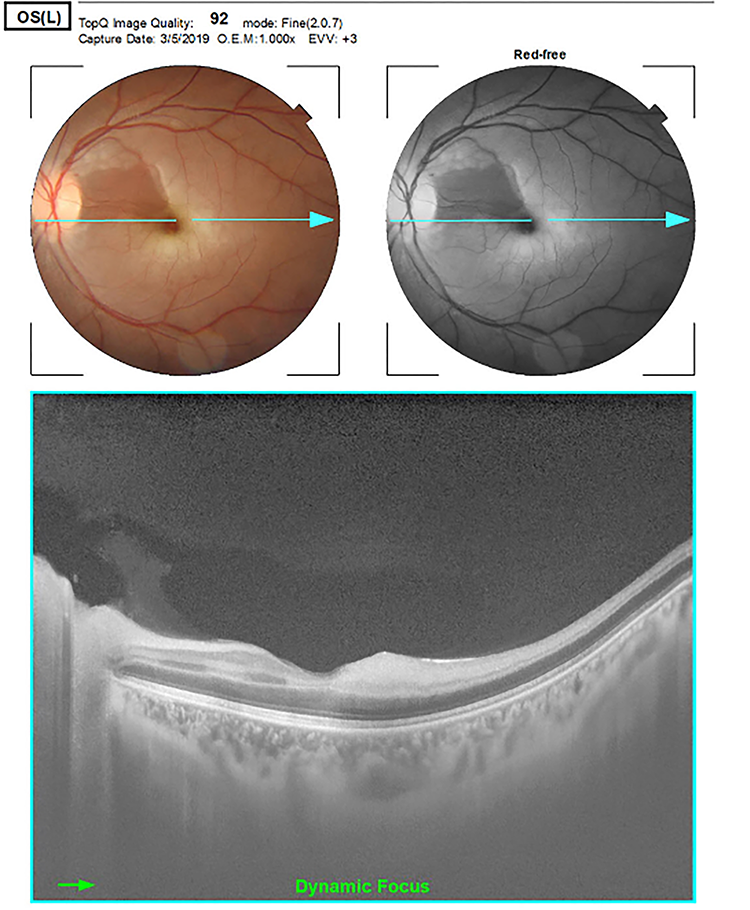

Paciente femenino de 29 años con embarazo (10,3 semanas) con historia de amaurosis fugaz de pocos minutos de duración con persistencia de escotoma del ojo izquierdo (OI). Ocho días luego del inicio de síntomas la paciente acude al servicio de urgencias oftalmológicas por pérdida súbita, indolora y severa de la agudeza visual (AV) en el OI. Antecedentes médicos, obstétricos y oculares sin datos de valor. Al examen físico se encontró agudeza visual mejor corregida de movimientos de manos en OI y 20/25 (Snellen) en ojo derecho (OD). El segmento anterior en ambos ojos (AO) sin alteraciones con defecto pupilar aferente grado 3 en OI. Presión intraocular (PIO) dentro de los parámetros normales. El examen del fondo de ojo del OI mostró palidez generalizada de la retina con engrosamiento macular que respetaba un área bien delimitada de retina perfundida de aspecto y coloración normal, en parte del haz papilomacular gracias a la permeabilidad de la arteria ciliorretinal, que es más evidente en la fotografía aneritra (fig. 1); mientras el OD estaba sin alteraciones.

Figura 1. Fotografía fundoscópica que muestra la retina pálida, edematizada, con la coloración rojiza normal conservada en el área correspondiente a la arteria ciliorretinal.

La tomografía de coherencia óptica mostró aumento de la reflectividad y engrosamiento generalizado de las capas internas de la retina temporal que produce un efecto de atenuación en las capas externas. La morfología y el grosor de la retina nasal eran de características normales (fig. 2). No se realizó angiografía fluoresceínica por estar desaconsejada en el embarazo.

Figura 2. OCT que muestra una banda hiporreflectiva en las capas externas de la retina.